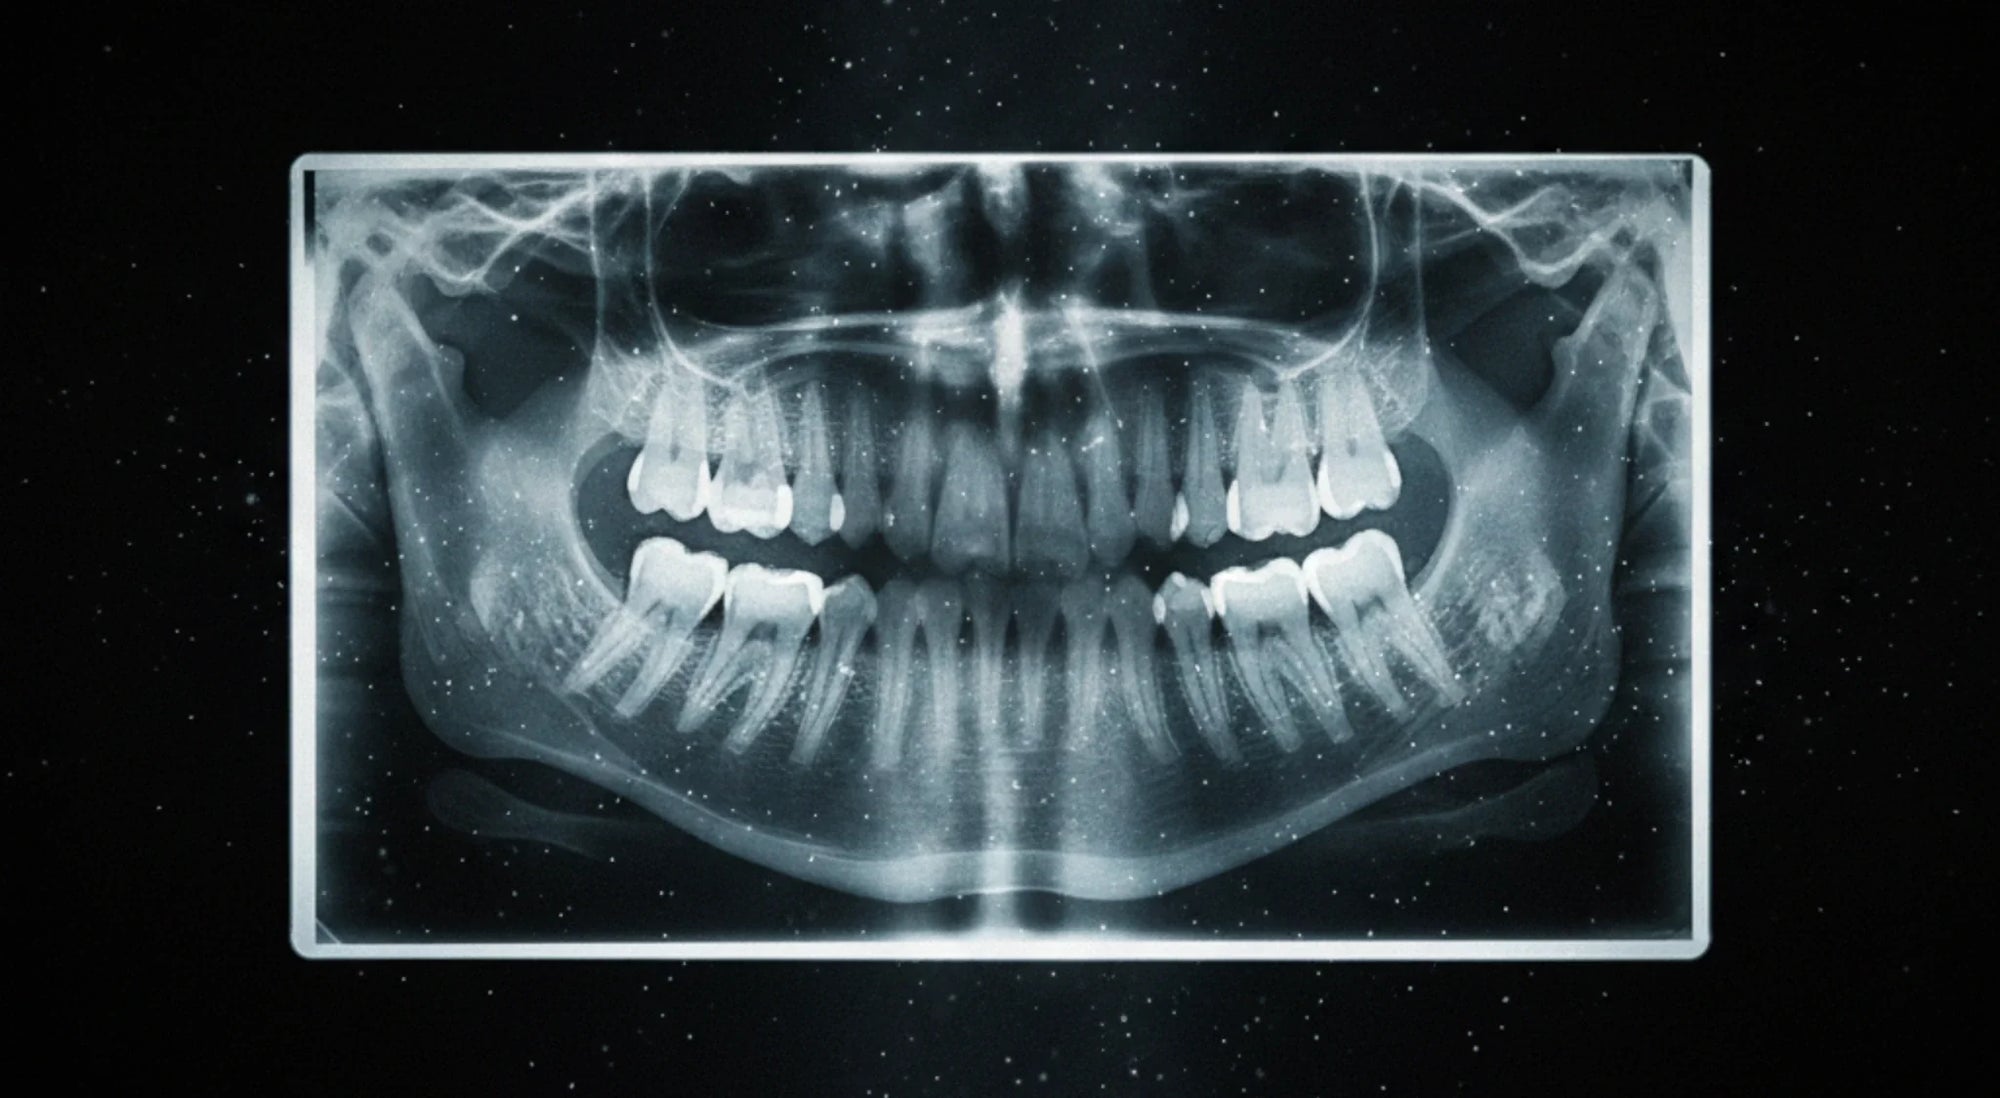

Periodontal disease often develops quietly. Teeth may look white and clean to you, while inflammation and early bone loss progress below the gumline in ways only a dental exam and X‑rays can reliably detect.

• Possibly take updated X‑rays to compare bone levels with your last visit and check for any new bone loss.

Yes, asking for X‑rays is useful. They help you and your dentist track bone levels over time and spot changes that aren’t visible just by looking in the mirror.